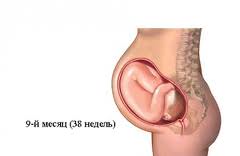

Розвиток дитини в 9 місяців вагітності

9 місяць - пологи можуть початися практично в будь-який час. Малюк вже повноцінний і готовий до життя. Живіт опустився, тому вагітній стає легше дихати. На 9 місяць дитина приймає в матці родову позицію: його головка опущена до грудей і розташовується в тазі, кінцівки наближені до тіла. У даній позиції йому найпростіше перебувати в щільному матці, і з такого становища йому найзручніше з'явитися на світло.

9 місяць - дитина повністю дозрів, його вага приблизно 2500-4100 г, а зріст 47-56 см. Кожен день дитина набирає 15-30 м

На 9 місяць у дитини майже немає гармата, у нього світла шкіра, а підшкірний жир надає йому припухлість на щічках, попі і спині. Сировідной мастила практично немає на тілі, вона залишається тільки на складках. При появі на світ дитина видає гучний крик, у нього розвинені навички дихання і смоктання.

На 9 місяць у малюка повністю сформовані статеві органи. У кишечнику збирається кал, який дитина вивільнить після появи на світло. Його печінку накопичує залізо. Легкі повністю сформувалися, серце готується до самостійного функціонування. Після того як малюк з'явиться на світ, в ньому зімкнуться обхідні шляхи і воно буде складатися з 4 повноцінних відгороджених камер.